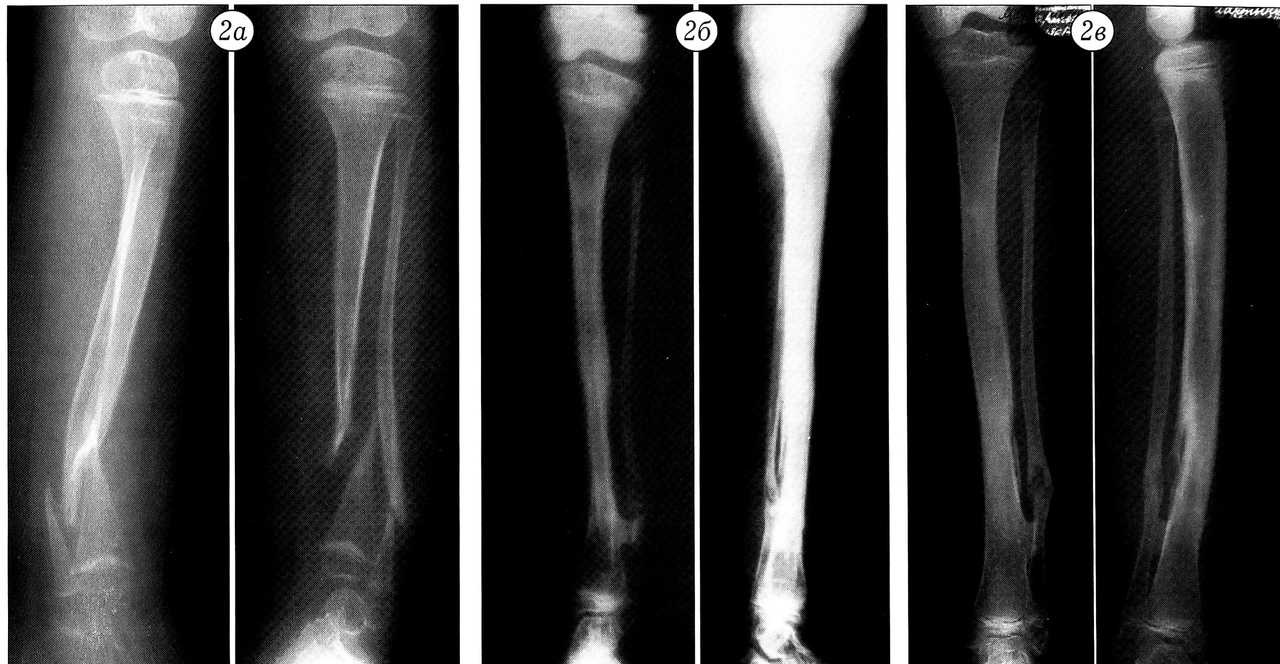

Наши многолетние наблюдения показали, что диафизарным отделом малоберцовой кости с питающим ее сосудистым пучком можно замещать обширные дефекты бедра, большеберцовой, плечевой кости и костей предплечья. После приживления трансплантат под действием функциональной нагрузки утолщается, приближаясь по размерам и форме к кости, дефект которой им замещается (рис. 1). Особенно показана такая тактика при больших дефектах костей предплечья и плеча любого генеза в сочетании с плохой васкуляризацией тканей, а также при врожденных ложных суставах (рис. 2).

Рис. 2. Рентгенограммы голени больной с врожденным ложным суставом. a — до аутопластики; б — через 7 мес после аутопластики васкуляризованным трансплантатом из диафиза малоберцовой кости;в — через 10 лет: восстановлены размер и форма большеберцовой кости.